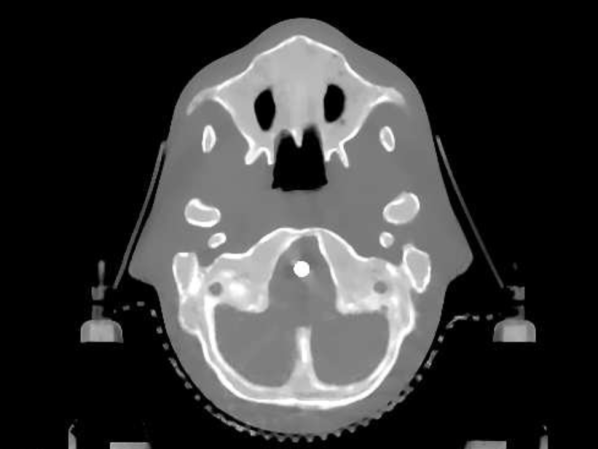

The data we used for our numerical reconstruction test were derived from the Adult Reference Computational Phantom (ICRP Publication 110,, 2009), which is a segmented image of defined density and chemical composition to represent real tissues. To investigate the ability to image metal implants, we inserted a pair of prosthetic hip joints (marked in green) with a solid titanium pin and shell. The slices through the chest and pelvis—which are the images we selected for testing—are shown in Figure 8. The resolution is 299×137299137299\times 137.

Refer to caption

(a) Chest test image

(b) Pelvis test image

Figure 8: Experimental data used: (a) is the oracle chest electron density; and (b) is the oracle pelvis electron density; both have a with display window of [0.8,1.2]